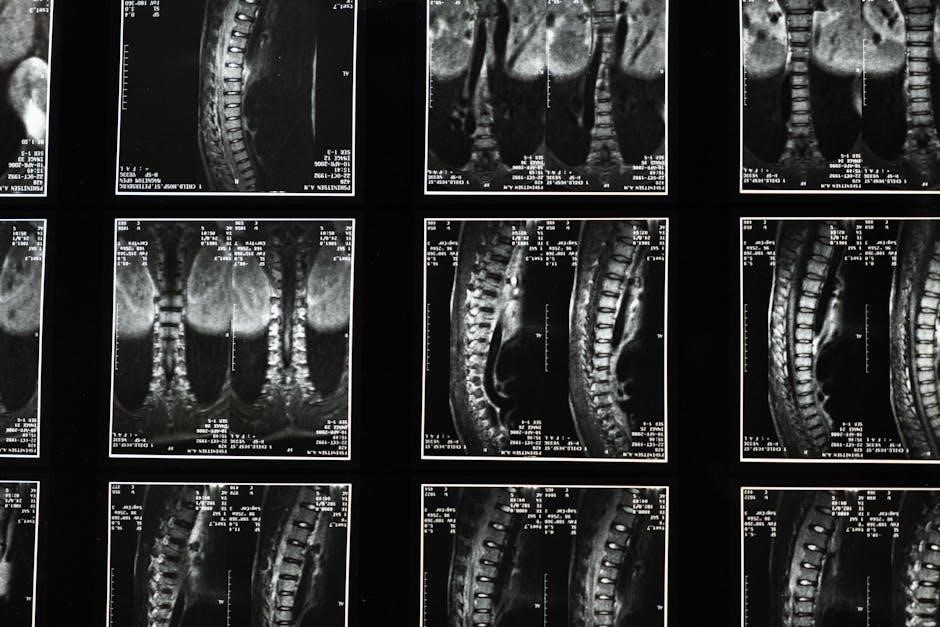

Targeting Brain Circuits: Globus Pallidus & Subthalamic Nucleus

The efficacy of MRgFUS in treating cervical dystonia hinges on the precise targeting of specific brain circuits implicated in the disorder’s pathophysiology. Current research and clinical practice primarily focus on two key targets: the globus pallidus and the subthalamic nucleus. These deep brain structures play critical roles in motor control and are often dysfunctional in individuals with dystonia.

The globus pallidus, a component of the basal ganglia, is involved in regulating movement and suppressing unwanted motor activity. Lesioning the globus pallidus can help alleviate dystonic symptoms by disrupting these abnormal neural pathways. Similarly, the subthalamic nucleus, also part of the basal ganglia, plays a crucial role in regulating movement initiation and execution. Targeting this structure can modulate neuronal activity and reduce the severity of dystonia.

The selection of the optimal target – globus pallidus or subthalamic nucleus – is individualized, based on a thorough assessment of the patient’s specific symptoms and the underlying neural circuitry contributing to their dystonia. Precise MRI guidance is essential to ensure accurate targeting and minimize off-target effects, maximizing therapeutic benefit.

Temperature Increase & Clinical Monitoring

During the MRgFUS procedure for cervical dystonia, a carefully controlled temperature increase is induced within the targeted brain tissue – either the globus pallidus or subthalamic nucleus – to create a focused lesion. This thermal ablation is achieved through the convergence of focused ultrasound waves. Real-time MRI thermometry is paramount, continuously monitoring the temperature changes at the anatomical target with exceptional precision.

The temperature is incrementally increased, and crucially, patients are meticulously monitored clinically after each temperature increment. This allows clinicians to assess for any immediate neurological changes or adverse effects, ensuring patient safety throughout the procedure. The goal is to achieve a therapeutic temperature sufficient to create a lesion, while avoiding excessive heating that could damage surrounding tissues.

Continuous clinical monitoring involves regular neurological examinations, assessing motor function, and evaluating for any emerging symptoms. This iterative process of temperature increase and clinical assessment is fundamental to optimizing treatment efficacy and minimizing potential risks, tailoring the procedure to each individual patient’s response.